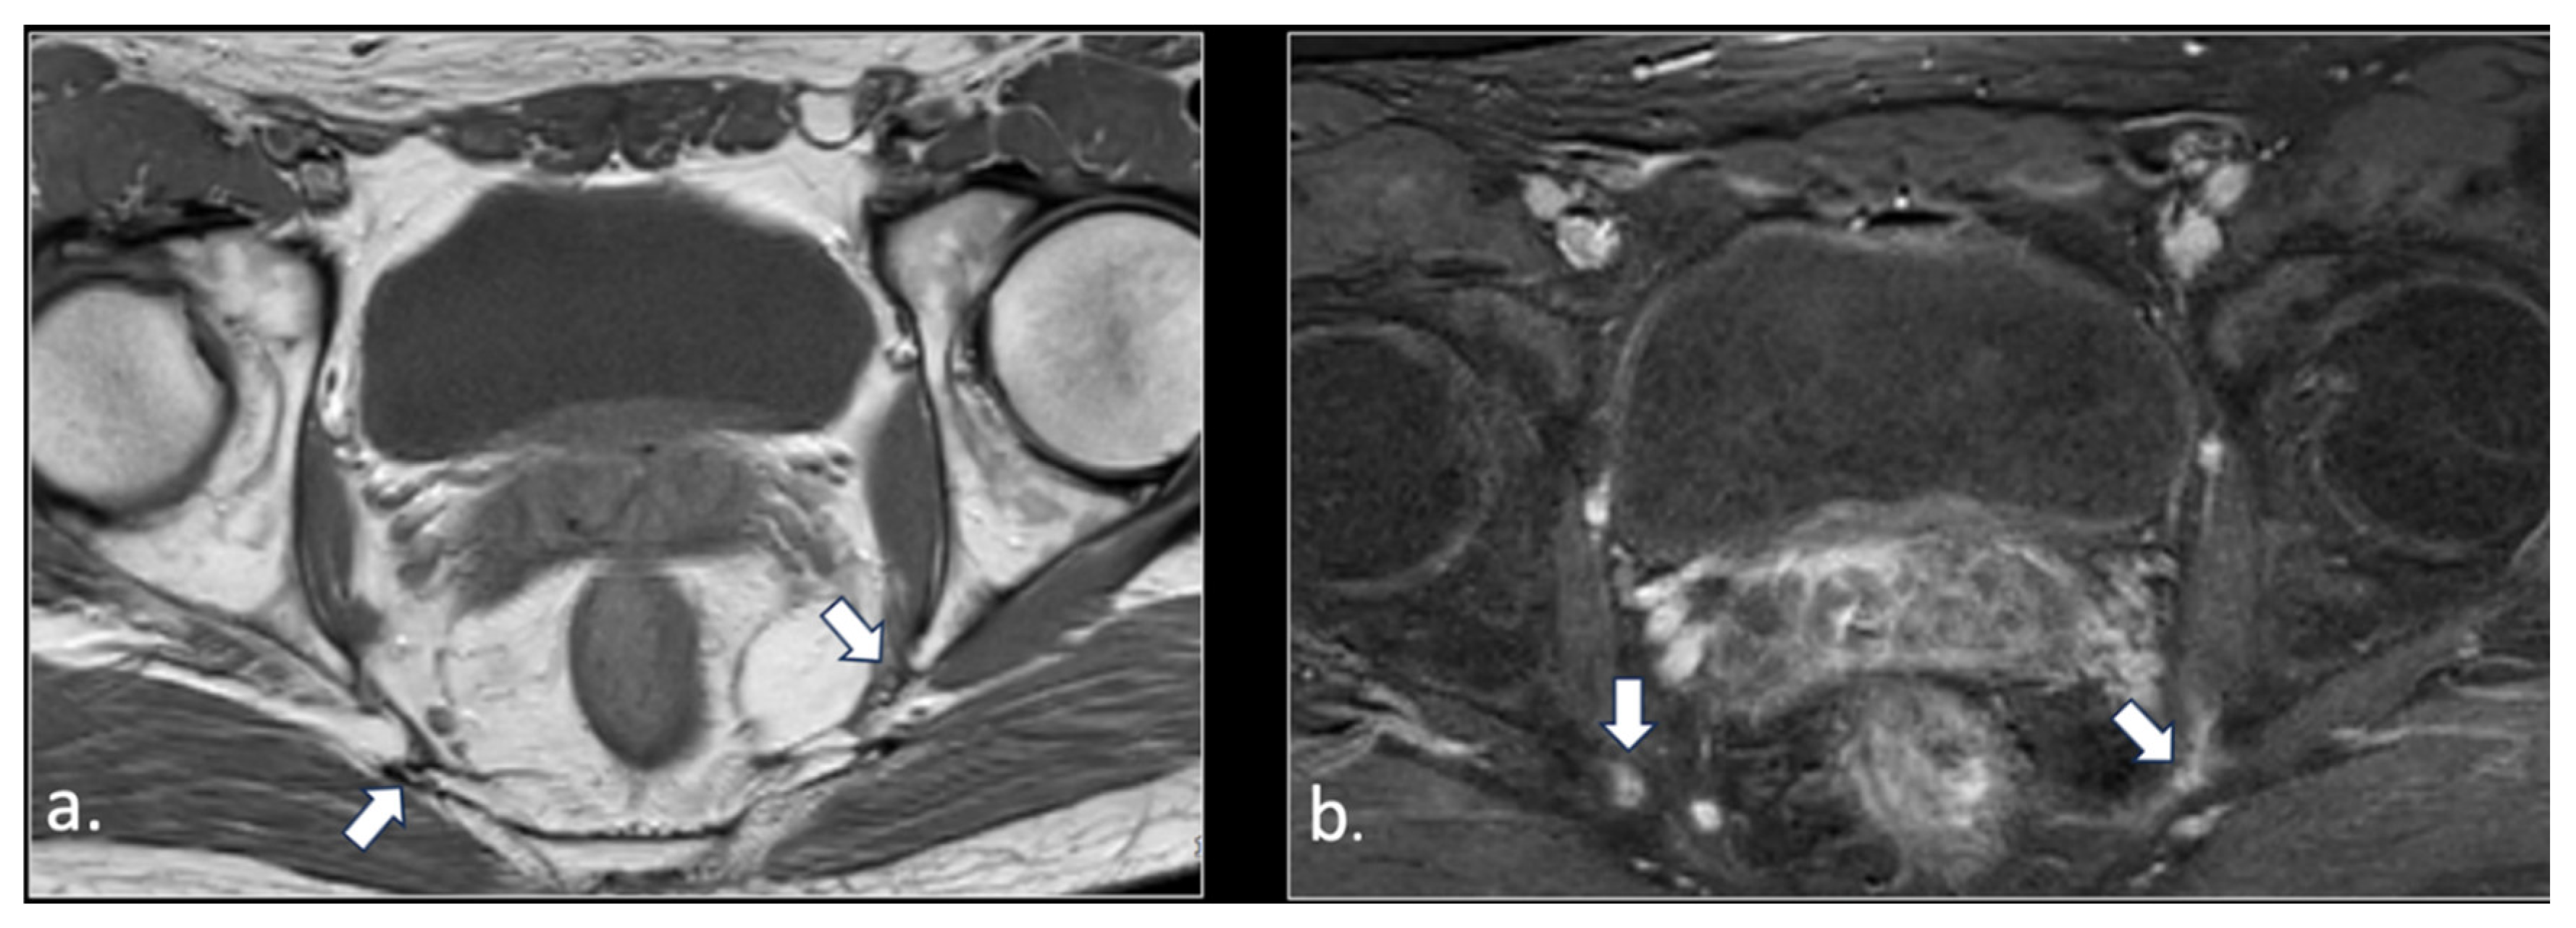

Figure 1.

Representation of the anatomic course of pudendal nerve at four fundamental levels. (a) Axial T1-weighted scan shows trough piriform muscles, lumbo-sacral (black arrow) and pudendal (arrowhead) plexuses of the anterior surface of left piriform muscle. On the right side, the S2 spinal root runs into the piriform muscle (arrow). This anatomic variation can predispose to nerve entrapment and pudendalgia. (b) Axial T1-weighted scan at the extra-pelvic course of the pudendal nerve. The nerve runs in the space between sacro-tuberous ligament posteriorly (arrow) and coccygeal muscle and sacro-spinous ligament (arrowhead) anteriorly. (c) Axial T1-weighted scan at the level of proximal Alcock’s canal. The pudendal neuro-vascular bundle runs close to the obturator internal muscle (arrow). The transverse course of inferior rectal neurovascular bundle can be seen into ischio-rectal fossa (arrowhead). (d) Axial T1-weighted scan at distal Alcock’s canal. At this level, it is difficult to detect the distal branches (arrowhead) of the pudendal nerve.